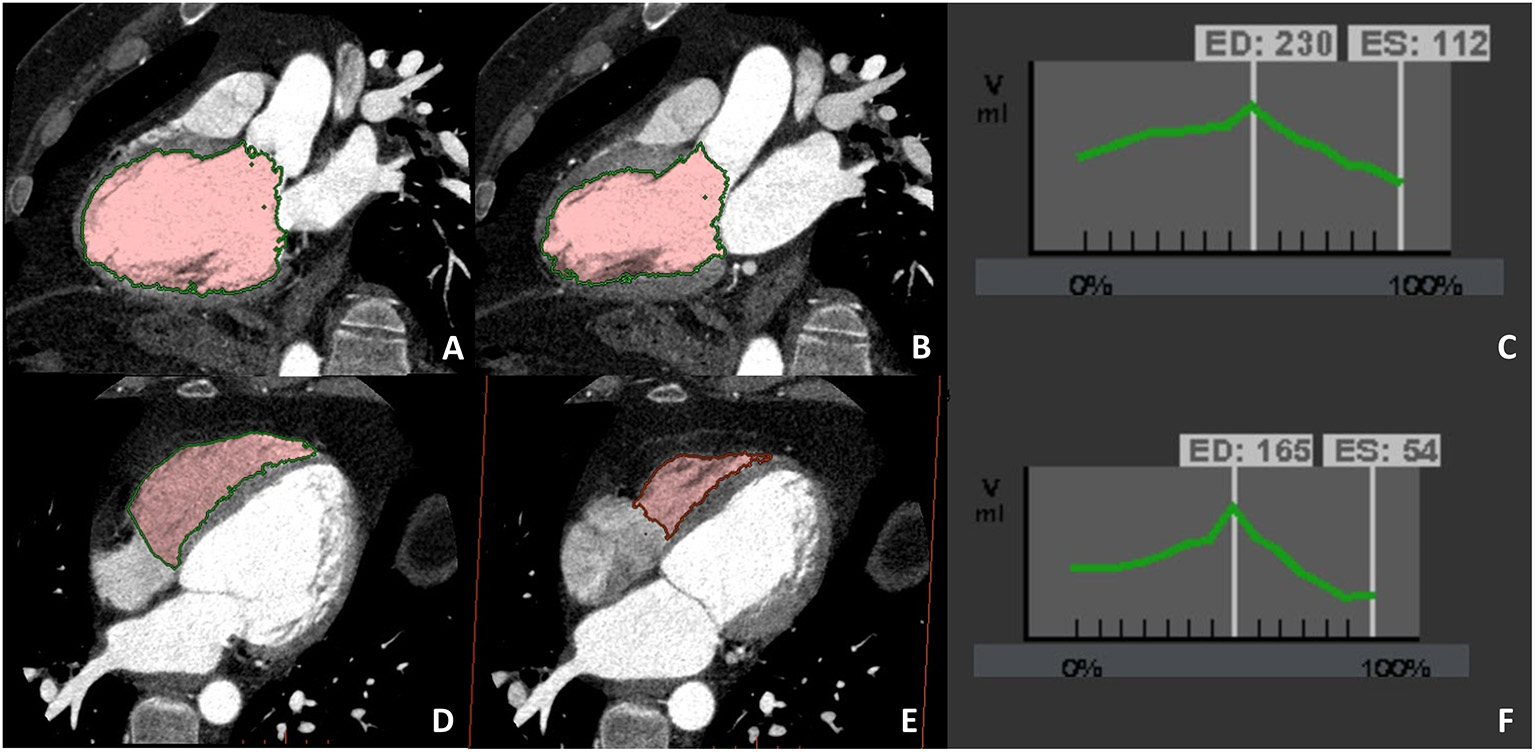

Figure 3

Dedicated cardiac CT (CCT) scan protocol for the comprehensive evaluation in DCM patients. In (A,B) a cardiac CT dedicated to coronary anatomy evaluation is shown; it is well evident how it is not possible to correctly identify the right ventricular border of the interventricular septum. In (C,D) a CT with dedicated acquisition protocol for biventricular volume and function in which all four chambers are opacified by contrast medium enabling correct right ventricular border identification. These examples highlight the need for a dedicated acquisition protocol for most of the non-coronary cardiac CT findings.

Figure 4

A case example of patients in which biventricular volume and function have been evaluated at CCT due to cardiac magnetic resonance (CMR) contraindication (claustrophobia). Biventricular balanced opacification enabled to correctly quantify both the left (panel A–C) and right (panel D–F) ventricular ejection fraction (LVEF 49%, RVEF 68%). Images were acquired during the entire cardiac cycle and the radiation dose needed for this evaluation was 7.5 mSv, heightening one of the main limitations to the routine clinical use of CCT for left ventricular evaluation.